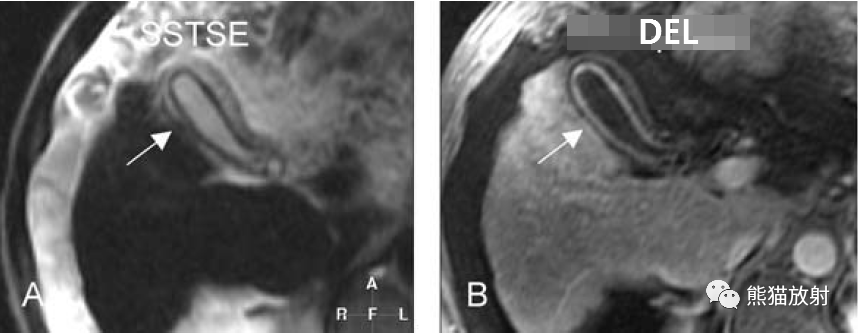

膽囊癌。A~D圖:上方層面,表現(xiàn)如上所述,形成腫物侵及肝臟。E、F圖:下方層面示膽囊壁不規(guī)則增厚,明顯不均質(zhì)強(qiáng)化。

T2壓脂(T2 fatsat):膽囊窩內(nèi)膽囊癌病變較肝臟為高信號,病變頂部向肝內(nèi)擴(kuò)展;

T1同相位(T1 in-phase):膽囊癌病變較肝臟為低信號;

增強(qiáng)動(dòng)脈期(ART):不均質(zhì)強(qiáng)化;

延遲期(DEL):部分廓清,部分持續(xù)強(qiáng)化。